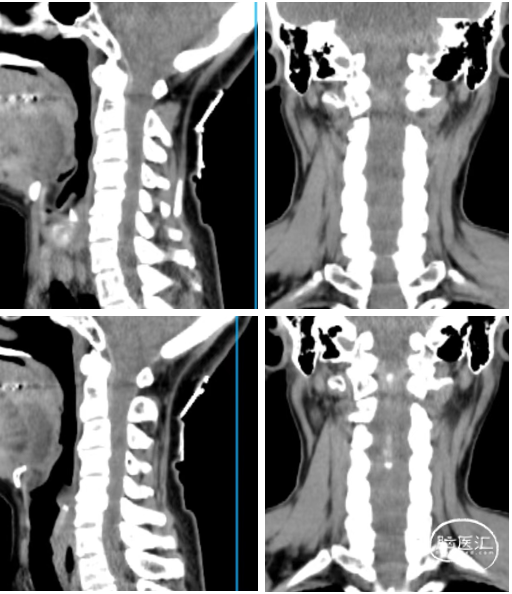

辅助检查:颈椎CT及MR示:脑干下份、C1-7水平脊髓上份见异常信号,累及长度约128mm,部分区域强化明显,内见病灶信号不均匀,增强见实性成分明显强化,相应水平脊髓肿胀等。

图1 颈椎CT及MRI示:脑干下份、C1-7及T1水平脊髓上份见异常信号,考虑室管膜瘤可能性大。